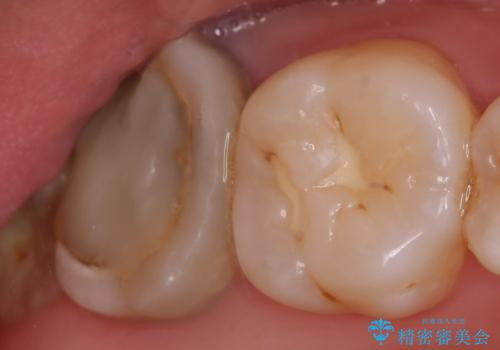

オールセラミッククラウン 鈍痛が続く奥歯の治療

- 他院にて右上7番目の歯の根管治療を行ったが鈍い痛みが治まらないので診て欲しいといらっしゃった方の症例です。

再根管治療を行い症状の消失を確認後、オールセラミッククラウンによる補綴を行いました。

今回用いたオールセラミッククラウンはジルコニアフレームという白い素材の上にセラミックを盛っているため、審美性が非常に高いのが特徴です。

また、ジルコニアは人工ダイヤモンドの材料にも使われているほど高い強度を持っており、そのためオールセラミッククラウンは審美性だけでなく、奥歯やブリッジの補綴も可能とするクラウンです。